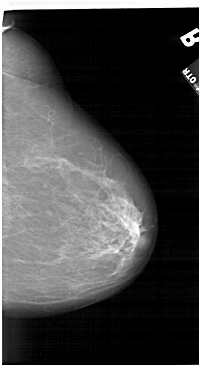

A_1124_1.RIGHT_MLO

RIGHT_MLO LINES 6361 PIXELS_PER_LINE 3751 BITS_PER_PIXEL 12 RESOLUTION 43.5 NON_OVERLAY

FILE: A_1124_1.LEFT_CC.OVERLAY

TOTAL_ABNORMALITIES 1

ABNORMALITY 1

LESION_TYPE CALCIFICATION TYPE PLEOMORPHIC DISTRIBUTION LINEAR

ASSESSMENT 4

SUBTLETY 1

PATHOLOGY MALIGNANT

TOTAL_OUTLINES 1

BOUNDARY